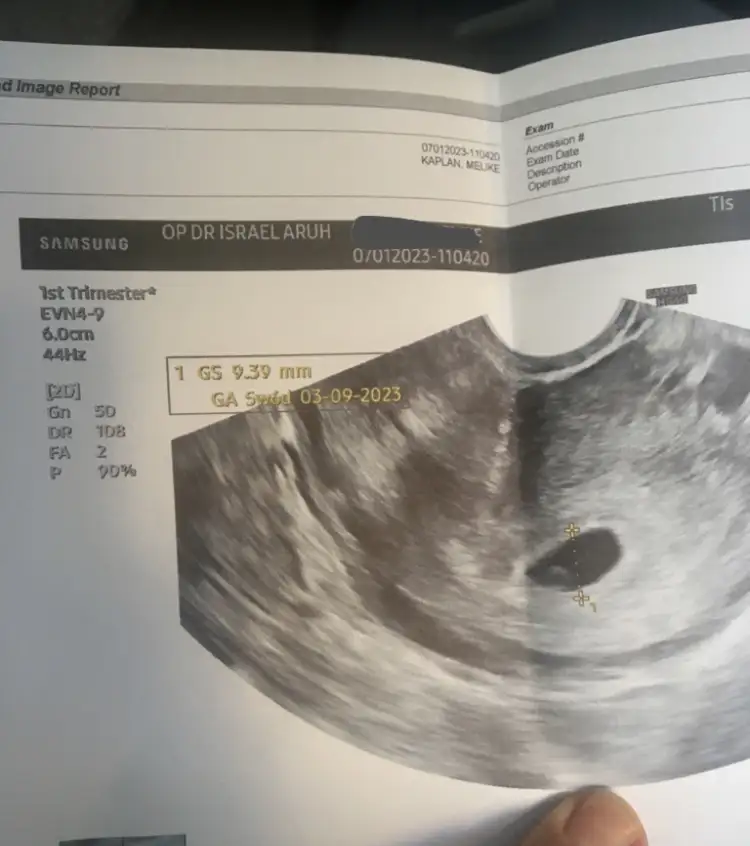

maşallah sizinki kac haftalıkKızlar bu da benim bıdık

Oy maşallah canımKızlar bu da benim bıdık

5+6 yazıyor kağıtta sat a göre 5+3 tu amamaşallah sizinki kac haftalık

Gözükür sizin de o zaman 5+6 yazıyor kağıtta sata göre 5+3 tuOy maşallah canımbende perşembe gideceğim doktora kaç haftalık. Ben bugün 5+0